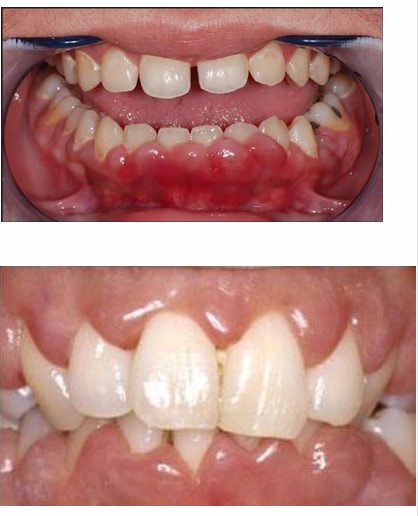

MFD EXAMS /23 6 1234567891011121314151617181920212223 You have 30 min to complete this exam. The timer will start once you begin Attention: Only a few minutes left! Please submit your answers soon. MFD 1 Get a quick sneak peek before the real exam !This trial quiz is designed to show you the question style, difficulty level, and how the options will appear on the platform. 1 / 23 1. What is the lethal dose and toxic dose of fluoride, management? Check 2 / 23 2. What the advantage of silver diamine over other methods and disadvantages ? Check 3 / 23 3. Method of topical fluoride application with concentration ? Check 4 / 23 4. What will happen if left untreated? Check 5 / 23 5. What changes that will happen if the habit stopped? Check 6 / 23 6. Give 3 of your initial stage of treatment? Check 7 / 23 7. What are the causes? Check 8 / 23 8. What is this? Check 9 / 23 9. Then they specified the type of pain and asked about the diagnosis Check 10 / 23 10. What other tests to check vitality of the pulp? Check 11 / 23 11. What are the factors will govern the Rx of Posterior cross bite ? Check 12 / 23 12. What are the factors that govern the treatment of anterior cross bite? Check 13 / 23 13. Name the appliance that you can use to treat this case? Check 14 / 23 14. Name 3 causes? Check 15 / 23 15. Name the most important clinical diagnostic information you need to know. (check RCSI intensive course )? Check 16 / 23 16. What do you see? Check 17 / 23 17. What is your treatment? Check 18 / 23 18. Name the investigations needed? Check 19 / 23 19. causes for gingival enlargement ? Check 20 / 23 20. What is the common side effect of this drug? Check 21 / 23 21. Name the drug that he may take to treat this condition? Check 22 / 23 22. The patient may have what? Check 23 / 23 23. What is this clinical condition? Check /31 2 12345678910111213141516171819202122232425262728293031 You have 30 min to complete this exam. The timer will start once you begin Attention: Only a few minutes left! Please submit your answers soon. MFD 2 Get a quick sneak peek before the real exam !This trial quiz is designed to show you the question style, difficulty level, and how the options will appear on the platform. 1 / 31 1. Mention 2 fixed space maintainers and 2 removable space maintainers other from mentioned : Check 2 / 31 2. Other space maintenance used for child lost primary second molar E before the eruption of the permanent molars ? Check 3 / 31 3. What are the difference between nance appliance and Transpalatal arch Check 4 / 31 4. What material used to attach band? Check 5 / 31 5. What instruction you give to patient? Check 6 / 31 6. Name other fixed space maintainer used in upper jaw and mechanism of their action? Check 7 / 31 7. What component of this appliance? Check 8 / 31 8. What is this appliance , for what its used ? Check 9 / 31 9. Treatment? Check 10 / 31 10. Define Abrasion and Erosion? Check 11 / 31 11. What does this picture show? Check 12 / 31 12. what investigations you can do ? Check 13 / 31 13. Drugs can lead to lichenoid reaction Check 14 / 31 14. What extra oral features in “ Lichenoid reaction )? Check 15 / 31 15. What microscopical features of it ( licheonoid reaction )? Check 16 / 31 16. Definitive diagnosis ? Check 17 / 31 17. Mention type of suggested biopsy ? Check 18 / 31 18. Mention 4 differential diagnosis ? Check 19 / 31 19. Mention 4 questions you will ask the patient ? Check 20 / 31 20. Give 4 intraoral decription of what you see ? Check 21 / 31 21. What the other surgery can be performed to make prothesis? Check 22 / 31 22. Can this tooth stand with fixed prothesis? (in the opg )à taken from Malek file ? Check 23 / 31 23. Radiograph of missing multiple teeth consider it according to Antes law? ON which tooth you will make Abutment ? Check 24 / 31 24. What is Antes law? Check 25 / 31 25. What is best one to use as abutment in fixed prosthesis A or B? Check 26 / 31 26. What relevance of this picture? Check 27 / 31 27. What’s complication of doing surgery in this area floor of mouth? Check 28 / 31 28. Other 2 radiograph needed in diagnosis? Check 29 / 31 29. Give 4 differential diagnosis? Check 30 / 31 30. What can you see ? Check 31 / 31 31. What is the name of radiograph? Check Your score is /30 1 123456789101112131415161718192021222324252627282930 You have 30 min to complete this exam. The timer will start once you begin Attention: Only a few minutes left! Please submit your answers soon. MFD 3 Get a quick sneak peek before the real exam !This trial quiz is designed to show you the question style, difficulty level, and how the options will appear on the platform. 1 / 30 1. Treatment? Check 2 / 30 2. Histopathology? Check 3 / 30 3. Differential diagnosis Check 4 / 30 4. Clinical features’? Check 5 / 30 5. Patient said, this lesion is very frequent, why? Check 6 / 30 6. What are the causes for ulcers? Check 7 / 30 7. Patient have other signs like uveitis ,Genital ulcerations which syndrome he had ? Check 8 / 30 8. Name of the lesion ? Check 9 / 30 9. Mention some TMJ movement ? Check 10 / 30 10. Blood supply ? Check 11 / 30 11. Nerve supply ? Check 12 / 30 12. Which muscles close? Check 13 / 30 13. Action of open and open wide? Check 14 / 30 14. Why it’s Atypical joint ? Check 15 / 30 15. Name of the ligaments ? Check 16 / 30 16. What would be your management? Check 17 / 30 17. Bacteria involved Check 18 / 30 18. Which type of Periodontitis? Check 19 / 30 19. Treatment? Check 20 / 30 20. Histopathology? Check 21 / 30 21. Differential diagnosis? Check 22 / 30 22. Clinical features? Check 23 / 30 23. What are the time frames for making a complaint? Check 24 / 30 24. What are the 3 points related to negligence? Check 25 / 30 25. Who is allowed access to the patient records? Check 26 / 30 26. How to differentiate if it is upper or lower motor neuron lesion? Check 27 / 30 27. Management? Check 28 / 30 28. What are the causes? Check 29 / 30 29. What should you advise the patient to do? Check 30 / 30 30. What is this lesion? Check Your score is /24 1 123456789101112131415161718192021222324 You have 30 min to complete this exam. The timer will start once you begin Attention: Only a few minutes left! Please submit your answers soon. MFD 4 Get a quick sneak peek before the real exam !This trial quiz is designed to show you the question style, difficulty level, and how the options will appear on the platform. 1 / 24 1. What does MRONJ stands for? Check 2 / 24 2. Give definition for MRONJ Check 3 / 24 3. For what medical problems these medications are used? Check 4 / 24 4. Stages of MRONJ 3 Check 5 / 24 5. What’s this appliance? Check 6 / 24 6. At what age is it used? Check 7 / 24 7. What type of malocclusion is it used to treat? Check 8 / 24 8. What changes will produce? (4 options) Check 9 / 24 9. Disadvantages? Check 10 / 24 10. Why is it flabby tissue? Check 11 / 24 11. what is this condition called? Check 12 / 24 12. Causes ? Check 13 / 24 13. Clinical Features ? Check 14 / 24 14. How to avoid it ? Check 15 / 24 15. Management? Check 16 / 24 16. Ideal post length and width Check 17 / 24 17. Definition of Ferrule it’s the Check 18 / 24 18. What is the importance of the ferrule effect ? Check 19 / 24 19. Describe the radiolucency? Check 20 / 24 20. Give 6 differential diagnosis? Check 21 / 24 21. Give 5 radiographical features? Check 22 / 24 22. What is the difference between incisional and excisional biopsy? Check 23 / 24 23. What other 2 plain radiographs we can we can take? Check 24 / 24 24. ALARA? Check Your score is /22 1 12345678910111213141516171819202122 You have 30 min to complete this exam. The timer will start once you begin Attention: Only a few minutes left! Please submit your answers soon. MFD 5 Get a quick sneak peek before the real exam !This trial quiz is designed to show you the question style, difficulty level, and how the options will appear on the platform. 1 / 22 1. . Types of external root resorption? Check 2 / 22 2. The cause of root resorption in the pic? Check 3 / 22 3. How you will treat it? Check 4 / 22 4. What is this probe? Check 5 / 22 5. What is the mark a ? Check 6 / 22 6. What is the mark b ? Check 7 / 22 7. What is the score from the given reading? Check 8 / 22 8. What is the treatment need of the patient according to the score? Check 9 / 22 9. What is the differential diagnosis ? Check 10 / 22 10. Four clinical features of the lesion? Check 11 / 22 11. Treatment ? Check 12 / 22 12. Describe what do you see? Check 13 / 22 13. Causes for it ? Check 14 / 22 14. Treatment ? Check 15 / 22 15. Picture of patient with Anaphylaxis…after taking Check 16 / 22 16. What is diagnosis? - Check 17 / 22 17. What a the signs of Anaphyalxis reactions ? Check 18 / 22 18. What first line of treatment? Dose? Route of Adminstration? Check 19 / 22 19. Other drug used? Check 20 / 22 20. What are expected complications if not treated ? Check 21 / 22 21. What precautions should be made to prevent anaphylaxis reaction ? - Check 22 / 22 22. Name 10 drug in emergency used with their route of Administration and their condition they use in? Check Your score is /36 1 123456789101112131415161718192021222324252627282930313233343536 You have 30 min to complete this exam. The timer will start once you begin Attention: Only a few minutes left! Please submit your answers soon. MFD 6 Get a quick sneak peek before the real exam !This trial quiz is designed to show you the question style, difficulty level, and how the options will appear on the platform. 1 / 36 1. . What are cases that you have to extract the primary tooth? Check 2 / 36 2. D. What are the indications for extraction? Check 3 / 36 3. What are your treatment options? Check 4 / 36 4. Investigations? Check 5 / 36 5. Type of trauma? Check 6 / 36 6. Patient diagnosed with sjorgen syndrome Histology ? - Check 7 / 36 7. Patient diagnosed with sjorgen syndrome Mention four blood investigations ? Check 8 / 36 8. Patient diagnosed with sjorgen syndrome Mention two sites where can we take the biopsy Check 9 / 36 9. Patient diagnosed with sjorgen syndrome How can you differentiate between primary and secondary ? Check 10 / 36 10. Gingival inflammation present in which syndrome Check 11 / 36 11. What is the treatment? Check 12 / 36 12. mention another connective tissue disease that can lead to lesions “ intraorally “ similar to the Lichen planus ? Check 13 / 36 13. what serious complication can arise from Erosive lichen planus ? Check 14 / 36 14. If it was atrophic lesion what histology might be seen ? Check 15 / 36 15. List the histological features of lichen planus ? Check 16 / 36 16. Lichen planus what dose it affect? Check 17 / 36 17. Age group commonly affected ? -ref SAQ Check 18 / 36 18. What are the clinical presentation ‘ types of lichen planus ‘ Check 19 / 36 19. What might you see in patient’s body that has a relation to this lesion? Check 20 / 36 20. What are the differential diagnoses? Check 21 / 36 21. Factors for platelet adhesion? Check 22 / 36 22. What can you see? Check 23 / 36 23. Other 2 process of hemostasis? Check 24 / 36 24. Two diseases in which they increase ? Check 25 / 36 25. Two diseases in which they decrease? Check 26 / 36 26. Medical term when they decrease? And if they increased Check 27 / 36 27. Function Check 28 / 36 28. Life span ? Check 29 / 36 29. From where they arise? Check 30 / 36 30. Normal number? Check 31 / 36 31. What are the function of the guiding plane ? Check 32 / 36 32. The success rate ? Check 33 / 36 33. Mention single extra preparation requirement for Resin bonded bridge in posterior teeth ? Check 34 / 36 34. Mention 5 preparation features of it? Check 35 / 36 35. Give two advantages of it ? Check 36 / 36 36. What’s the name of this prosthesis? Check Your score is /23 1 1234567891011121314151617181920212223 You have 30 min to complete this exam. The timer will start once you begin Attention: Only a few minutes left! Please submit your answers soon. MFD 7 Get a quick sneak peek before the real exam !This trial quiz is designed to show you the question style, difficulty level, and how the options will appear on the platform. 1 / 23 1. If the same scenario but the tooth is subluxated. What is the management? Check 2 / 23 2. Aim of this procedure Check 3 / 23 3. Steps to do this procedure? Check 4 / 23 4. Management? How to asses the vitality of the tooth Check 5 / 23 5. Mention factors that can affect the treatment plan ? Check 6 / 23 6. Identify the Kenneyd’s classification Check 7 / 23 7. Name its parts? Check 8 / 23 8. Uses of Surveyor Check 9 / 23 9. What is this ? Check 10 / 23 10. Criteria for hand piece sterilization Check 11 / 23 11. steps for wrapped instrument sterilization process ( ref : sterilization in SDCEP)? Check 12 / 23 12. What is the difference between sterilization and decontamination? Check 13 / 23 13. Optimal temperature & pressure & time for autoclave? Check 14 / 23 14. Difference between vacuum and non-vacuum autoclave in mechanism? Check 15 / 23 15. Optimum temperature? Check 16 / 23 16. Advantage of vaccum over non vaccum? Check 17 / 23 17. What is the significance of forehead wrinkling? Check 18 / 23 18. What is Ramsy haunt syndrome ? Rx ? and is it LMN or UMN ? Check 19 / 23 19. Enumerate 3 extracranial and intracranial causes for this ? Check 20 / 23 20. What are the branches of facial nerve? Check 21 / 23 21. Why do we suture the eye in a patient with Facial Palsy? Check 22 / 23 22. Differentiate between Upper and Lower Motor Neuron lesions? Check 23 / 23 23. What is shown in photograph? Check Your score is /27 0 123456789101112131415161718192021222324252627 You have 30 min to complete this exam. The timer will start once you begin Attention: Only a few minutes left! Please submit your answers soon. MFD 8 Get a quick sneak peek before the real exam !This trial quiz is designed to show you the question style, difficulty level, and how the options will appear on the platform. 1 / 27 1. Mention 4 diseases you would see in HIV Patients? Check 2 / 27 2. Give 2 differential diagnosis for this lesion? Check 3 / 27 3. Describe the lesion shown in Photograph B? Check 4 / 27 4. What is your diagnosis ? Check 5 / 27 5. Describe the lesion shown in Photograph A? Check 6 / 27 6. Disadvantages of gold ? Check 7 / 27 7. Ideal cement for All Porcelain? Check 8 / 27 8. Which cement would u use for high caries risk patient? Check 9 / 27 9. How much would you prepare for functional and non-functional cusps in Gold Crown? Check 10 / 27 10. what crown would you go for in bruxism patients out of these 3? Check 11 / 27 11. Name the 3 restorations? Check 12 / 27 12. After administering Local Anesthesia and deciding the choice of biopsy. What should be done before biopsying the lesion? Check 13 / 27 13. Name 2 systemic steroids with dosage you would recommend for this patient? Check 14 / 27 14. Name 2 topical steroids with dosage you would recommend for this patient? Check 15 / 27 15. What is your diagnosis? Check 16 / 27 16. Describe the lesion shown in photograph? Check 17 / 27 17. Name 5 options to increase retention and stability in class l Check 18 / 27 18. E. What is the function of the RPI system ? Check 19 / 27 19. What are the 2 disadvantages of the 2 restorations you mentioned? Check 20 / 27 20. What materials are your 2 restorations made of? Check 21 / 27 21. Other than implants what restoration would you place in this patient? Check 22 / 27 22. Which Kennedy’s classification is this? Check 23 / 27 23. Describe your management? Check 24 / 27 24. What may be the patient complaint? Check 25 / 27 25. What are the causes of this? Check 26 / 27 26. Describe what you see in the photograph? Check 27 / 27 27. which 4 examinations would you undertake? Check Your score is /31 0 12345678910111213141516171819202122232425262728293031 You have 30 min to complete this exam. The timer will start once you begin Attention: Only a few minutes left! Please submit your answers soon. MFD 9 Get a quick sneak peek before the real exam !This trial quiz is designed to show you the question style, difficulty level, and how the options will appear on the platform. 1 / 31 1. Describe what you see in the photograph? Check 2 / 31 2. Three other features of this syndrome ? Check 3 / 31 3. What is the medical condition associated with it “? Multiple OKC? Check 4 / 31 4. Where expansion occurs in the OKC ? Check 5 / 31 5. From which cells this lesion arises from? Check 6 / 31 6. What is your diagnosis? Check 7 / 31 7. What is the histopathology of the lesion shown in Histology slide? Check 8 / 31 8. Give 4 differential diagnosis? Check 9 / 31 9. What is the consequence of premature loss of deciduous teeth? Check 10 / 31 10. Identify those appliances and mention one use for each and mode of action? Check 11 / 31 11. What component of appliance no. 3 ? Check 12 / 31 12. How to overcome open bite disadvantage ? Check 13 / 31 13. What are Disadvantages of this appliance ? Check 14 / 31 14. What Ceph changes are expected while using this appliance ? Check 15 / 31 15. What is the construction of Twin Block Appliance? Check 16 / 31 16. What skeletal and dental changes are expected while using this appliance ? Check 17 / 31 17. What is the ideal age to treat this condition >? Check 18 / 31 18. Indications of the Twin Block Appliance? Two Check 19 / 31 19. Name the Appliance used to correct this? Check 20 / 31 20. What is the treatment? Check 21 / 31 21. How to prevent it Check 22 / 31 22. Mention three mechanisms of action of Fluoride? Check 23 / 31 23. What is the disease caused by excess Fluoride? Check 24 / 31 24. What are the risk factors associated with this patient? Check 25 / 31 25. Name the principal organism causing this? Check 26 / 31 26. what are the principles of the access cavity Check 27 / 31 27. What is your diagnosis? Check 28 / 31 28. What are principles of cavity preparation? Check 29 / 31 29. What is your Periapical diagnosis? Check 30 / 31 30. What is your Pulpal diagnosis? Check 31 / 31 31. Which test would you undertake? Check Your score is /21 0 123456789101112131415161718192021 You have 30 min to complete this exam. The timer will start once you begin Attention: Only a few minutes left! Please submit your answers soon. MFD 10 Get a quick sneak peek before the real exam !This trial quiz is designed to show you the question style, difficulty level, and how the options will appear on the platform. 1 / 21 1. Patient is 20 years old Mention two treatment options for this case ? Check 2 / 21 2. Patient is 20 years old What is the long term risk for not treating this case ? Check 3 / 21 3. Name of this appliance in the next picture? Check 4 / 21 4. What is the wire used ? Check 5 / 21 5. For which orthodontic cases this appliance is necessary ? Check 6 / 21 6. Why we use retainer ? Check 7 / 21 7. Describe what you see ? Check 8 / 21 8. Differential diagnosis:- Check 9 / 21 9. Name of those muscles ? Check 10 / 21 10. Name the Extrinsic muscles of the tongue? Check 11 / 21 11. . Which nerves innervate the Extrinsic muscles of the tongue?. Check 12 / 21 12. What is the somatic innervation of anterior 2/3 of tongue? Check 13 / 21 13. Which nerve supplies the posterior 1/3 of tongue?. Check 14 / 21 14. From which Pharyngeal arch posterior 1/3 derived from? Check 15 / 21 15. Mention the intrinsic muscle of the tongue ? Check 16 / 21 16. What is the name of this condition ? name the lesion on the skin ? Check 17 / 21 17. Mention 3 drugs that causing it ? Check 18 / 21 18. 2 infections associated with it Check 19 / 21 19. Mention 2 immediate treatment ? Check 20 / 21 20. Why this condition can be fatal ? Check 21 / 21 21. Which test would you undertake? Check Your score is